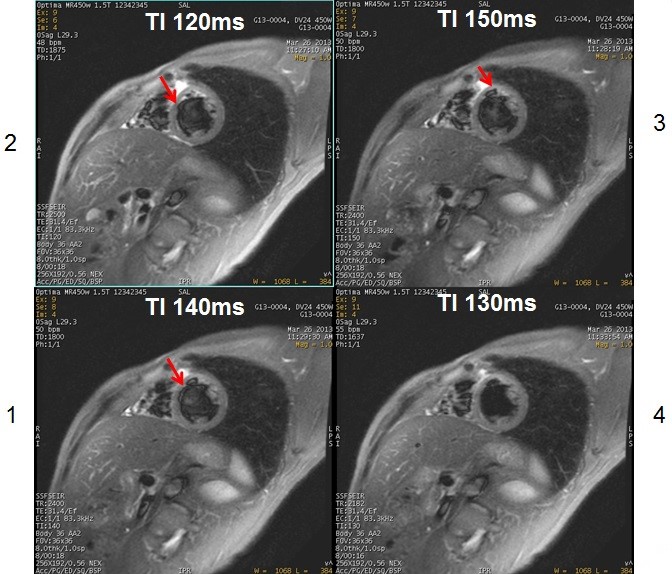

Figure 3. SSFSE-IR scans acquired with varying TI times

Table 2. Image legend Number Description 1,2,3 Note: the out-of-phase artifact seen when the TI is set to 120 ms, 140 ms and 150 ms.4 Optimum image quality when the TI is set to 130 ms.